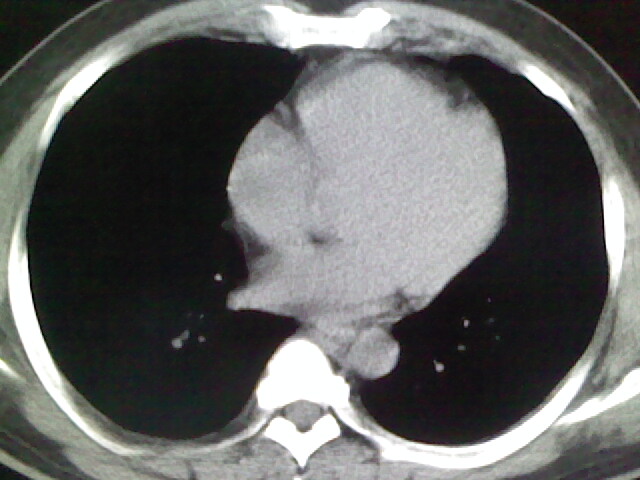

标题: CT17932:临床怀疑肺栓塞

男,34岁,自觉右侧胸痹,胸闷3天余

右侧肺动脉似见密度稍低影,请在机器的薄层上再看看有没有充盈缺损。